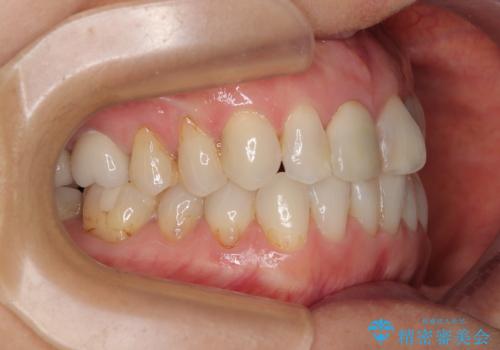

デコボコと銀歯 矯正治療とセラミック治療で綺麗な口元に

- 前歯のデコボコと口を開けたときに見える銀歯を気にして来院された患者様です。

ある程度デコボコが解消されれば大丈夫とのことで、インビザライン・モデレートパッケージを利用して歯列を整えて行くこととしました。

矯正治療後に銀歯をセラミッククラウンなどに置き換えていくと、どうしても後戻りを起こしてしまうため、矯正治療が概ね終了した時点で銀歯を全てセラミックとし、最後に仕上げでインビザラインにを用いて細かいデコボコを改善していくこととしました。

とても明るい口元となり、人目を気にせず、大きく口を開けて笑えるようになりました。